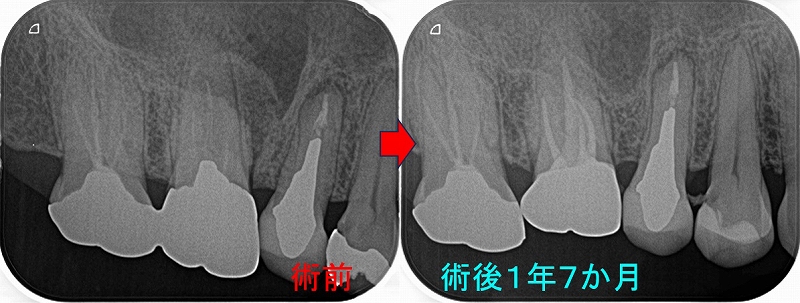

レントゲン

2026 EEdental NAY (1).jpg

第1大臼歯の黄色丸:C2~C3に及ぶ虫歯

第2大臼歯の赤丸:C4に近い虫歯

前に患者さんにも言いましたが、成功率を高くする為には

基本1つ次のステップの治療を行う事

つまり第1大臼歯は神経を取ってクラウン

第2大臼歯は抜歯

こうすることで将来トラブルの出る確率は多少減らせますが、

歯の寿命は確実に短くなりますし、咬みずらくなります。

ここが残りの人生を考えた際の選択になります。

短期予後を取るか!?それとも長い人生・将来的な事を考えた選択をするか!?

まず第一大臼歯はいつも通り

とりあえず神経を残す治療を行い、痛みが後で出てしまったら後で神経を取ると説明

2026 EEdental NAY (2).jpg